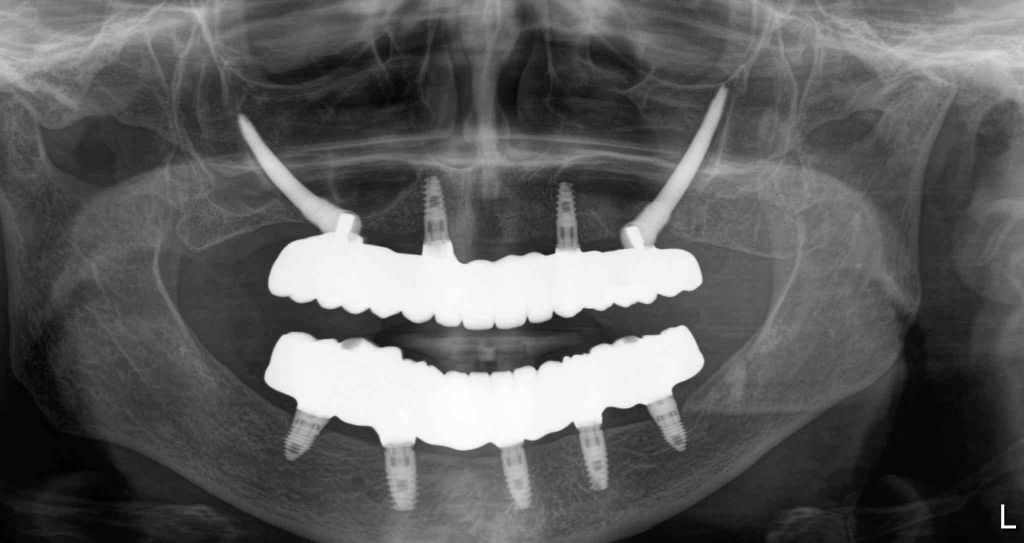

Zirconia bridge on Southern DC Implants